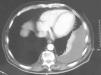

Los estudios de laboratorio (coagulación, dímero D, troponinas, hormonas tiroideas, antígeno carcinoembrionario, marcadores de colagenosis, serología de los virus de la inmunodeficiencia humana y de la hepatitis C, y sedimento de orina) fueron normales. Los resultados de la gasometría arterial basal fueron los siguientes: pH de 7,43, presión arterial de oxígeno de 75mmHg y presión arterial de anhídrido carbónico de 39mmHg. El Doppler de las extremidades inferiores y la gammagrafía pulmonar de ventilación-perfusión descartaron que el paciente presentara enfermedad tromboembólica. La prueba de la tuberculina y 3 baciloscopias de esputo fueron negativas. La tomografía computarizada confirmó el derrame izquierdo, sin engrosamiento pleural y con una mínima cantidad de líquido derecho (fig. 2), aumento de tamaño de las arterias pulmonares y adenopatías mediastínicas bilaterales menores de 1cm, sin signos de afectación parenquimatosa. En la toracocentesis se obtuvo un líquido transparente indicativo de trasudado (pH: 7,46; glucosa: 113mg/dl; lactatodeshidrogenasa: 98U/l; cociente pleuroplasmático de lactatodeshidrogenasa de 0,4 y de proteínas de 0,3; colesterol: 19mg/dl; adenosindesaminasa: 12U/l; 120leucocitos/μl con un 65% de linfocitos). La citología, la baciloscopia, los cultivos de 3 muestras de líquido y la biopsia pleural percutánea con aguja de Abrams descartaron la presencia de granulomas o de células atípicas. La broncoscopia no demostró alteraciones endobronquiales significativas, y la citología, el cultivo y la baciloscopia del broncoaspirado fueron negativos. El electrocardiograma mostraba ritmo sinusal con bloqueo completo de la rama derecha y complejo S1Q3T3. Posteriormente se realizó un ecocardiograma que confirmó la presencia de intensa insuficiencia tricuspídea, dilatación del ventrículo derecho e hipertensión pulmonar (presión arterial pulmonar estimada de 80mmHg), con insuficiencia mitral ligera-moderada, ventrículo izquierdo normal y fracción de eyección del 51%, sin derrame pericárdico.